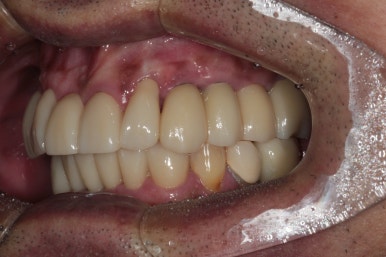

전체 임플란트 완성!!

어느 정도 적응이 되시면, 그 교합을 반영하여 최종 임플란트 크라운을 제작하게 되고 위와 같이 깔끔하게 완성되게 됩니다...

정면부터 비교도 안되게 좋아지신 것을 보실 수 있을겁니다.

위 앞니는 지르코니아 크라운으로, 아래 앞니는 지르코니아 브릿지로 새로 제작하여 적절한 overjet과 overbite를 형성하였고 상당히 자연스러운 외형을 갖춘 것을 보실 수 있을거에요.

또한 앞니를 크라운으로 제작하면서 치아의 색상도 보다 톤업해드렸고, 치아 배열도 가지런하게 그리고 치아 사이 공간도 모두 닫아드려 정말 한결 젊어졌다는 느낌이 듭니다.

임플란트를 엄청 많이 심지 않았지만, 적절한 개수를 식립해냄으로써 성인 남성도 식사가 가능할 정도의 임플란트 크라운을 제작해드릴 수 있었습니다.

앞니와 어금니를 한 번에 다 같이 만들었던 만큼, 크라운 색상의 조화가 기가막혀 진짜 내 이같아 보이네요..!!

이렇게 가지런한 치열은 바로 자신감을 가져다 주기도 합니다.